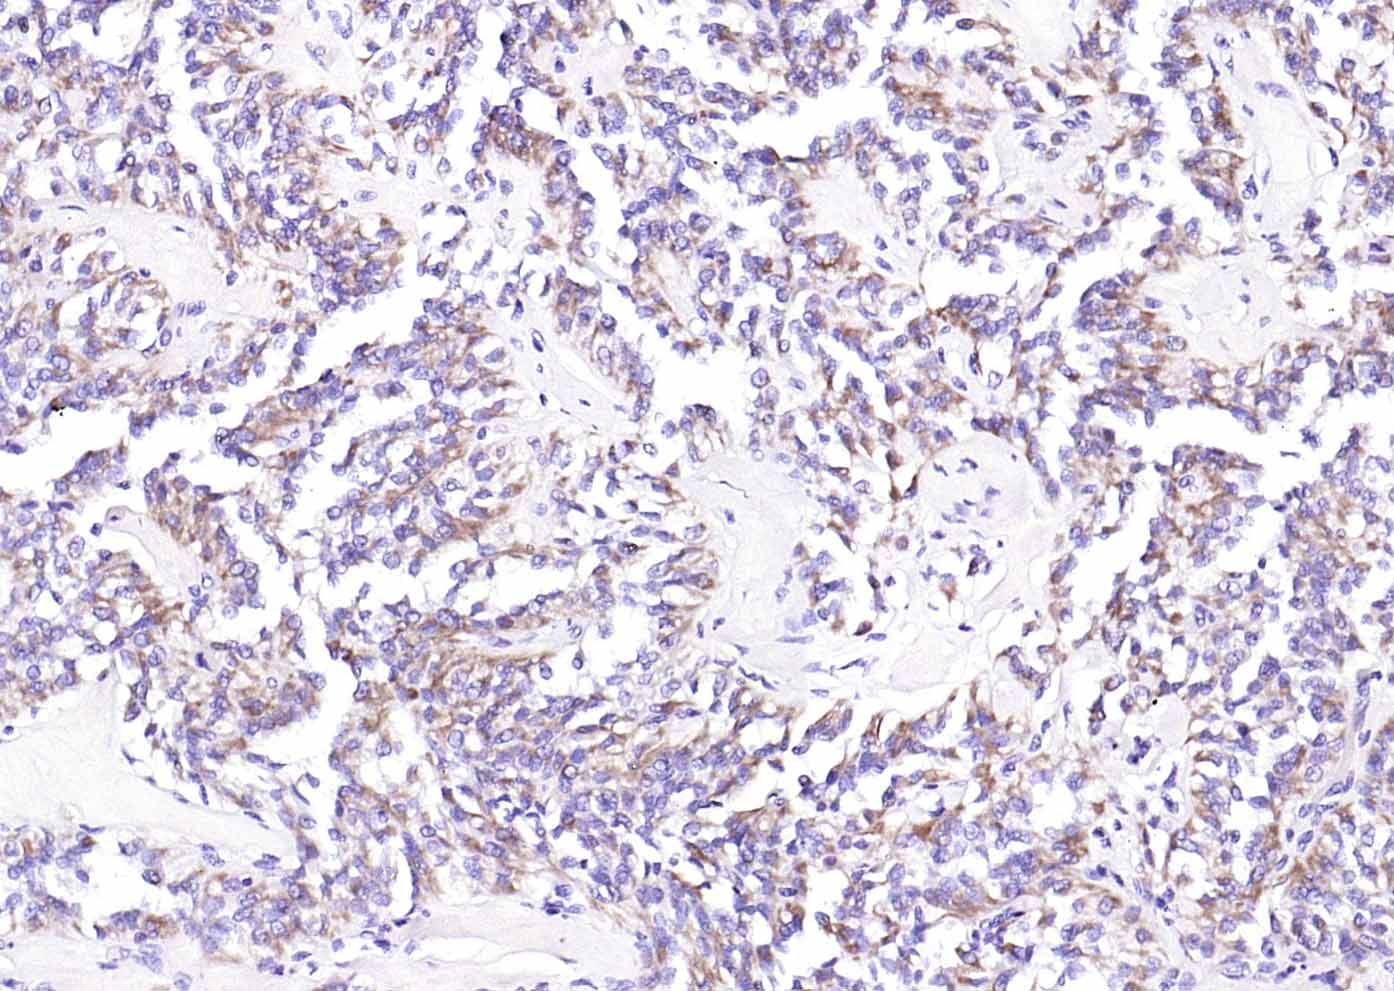

Paraformaldehyde-fixed, paraffin embedded (Human stomach); Antigen retrieval by boiling in sodium citrate buffer (pH6.0) for 15min; Block endogenous peroxidase by 3% hydrogen peroxide for 20 minutes; Blocking buffer (normal goat serum) at 37°C for 30min; Antibody incubation with (MUC5AC) Polyclonal Antibody, Unconjugated (bs-7166R) at 1:200 overnight at 4°C, followed by operating according to SP Kit(Rabbit) (sp-0023) instructionsand DAB staining.